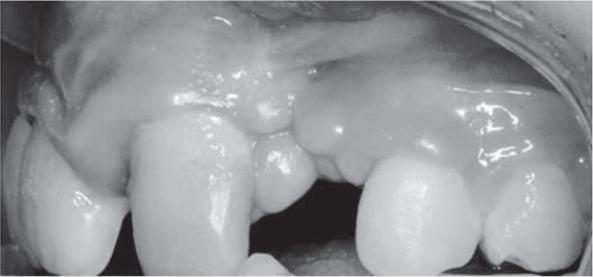

双侧唇腭裂生长发育期患者牙周组织的评估:一项初步研究。

Evaluation of periodontal tissues in growing patients with bilateral cleft lip and palate. A pilot study.

To evaluate the periodontal status, mucogingival parameters and oral hygiene in growing patients with bilateral cleft lip and palate.

Assessment was performed in 15 patients aged 6 to 18 years with a bilateral cleft. Records included probing pocket depth, clinical attachment level, keratinized gingiva, recession, vestibule depth, biotype, type of fraena, dental plaque and bleeding.

The mean scores of pocket depth were: 1.9 mm for central incisors, 1.6 mm for lateral incisors, 1.7 mm for canines, 2.0 mm for first premolars. There were only a few teeth with minimal attachment loss (1 mm). Gingival recessions were not recorded. High scores were recorded for the hygiene indicator, especially on the buccal, mesial and distal surfaces. Due to soft and hard tissue malformations, it was difficult to precisely assess the biotype and keratinized gingiva. However, keratinized gingiva was narrower near the teeth adjacent to the cleft. Similarly, the vestibule was shallower in this area. In 12 out of 15 children it was impossible to define the type of labial fraenum.

Evaluation of the periodontal status is important for successful comprehensive rehabilitation in cleft patients. Specific features of hard (alveolar process) and soft tissue (scars, unusual fraena) malformations caused by the cleft and previous surgical procedures have functional and morphological implications. Narrower gingiva and a shallower vestibule in the presence of dental plaque and bleeding are unfavourable conditions to maintain a healthy periodontium. It is essential to include periodontal assessment and preventive treatment to a comprehensive approach as early as possible.